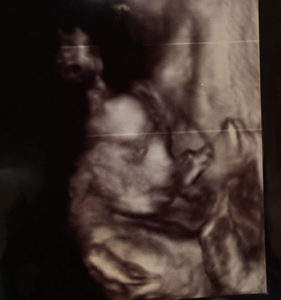

Our baby boy is weighing in at 3 pounds and 8 ounces!

I am anemic at this time with him but other than that he is growing just fine and is healthy so far.